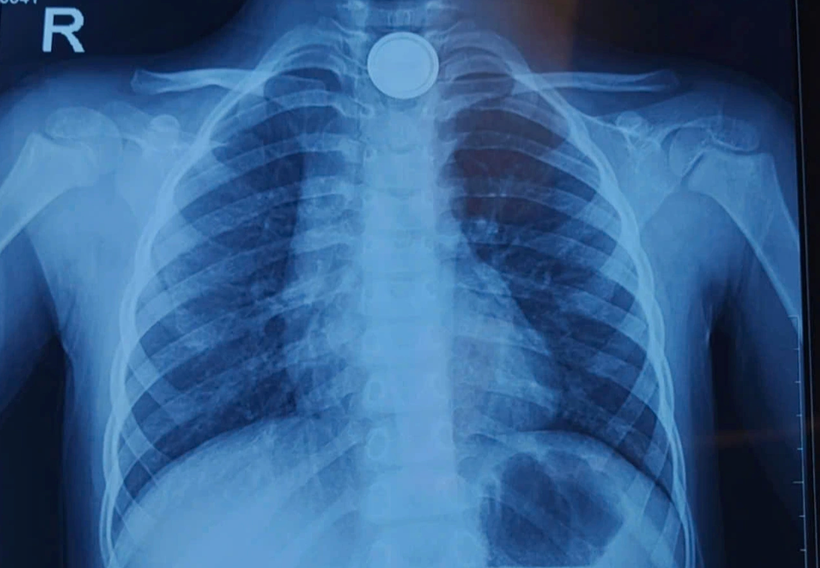

Phim chụp X-quang hình ảnh vị trí pin cúc áo trong cổ bệnh nhi. (Ảnh: BVCC)

Sau khi phát hiện sự việc, gia đình nhanh chóng đưa bé đến bệnh viện gần nhà, chụp X-quang phát hiện dị vật pin mắc ở thực quản ngang mức xương đòn.